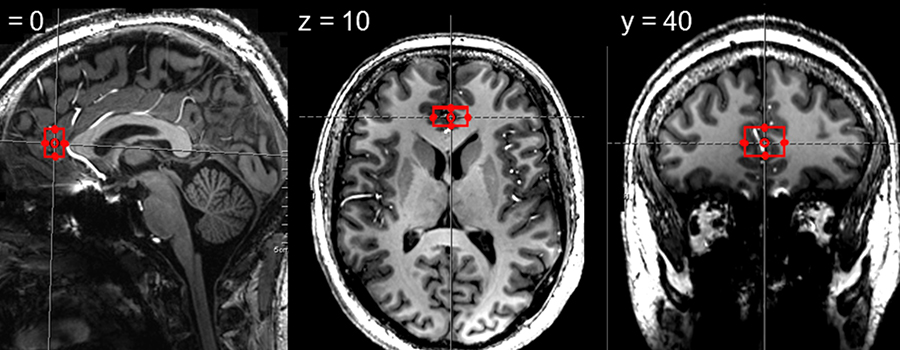

Abbildung des GehirnsIllustration: Region called pregenual anterior cingulate cortex where we measured neurometabolites in healthy participants and in participants with major depressive disorder.